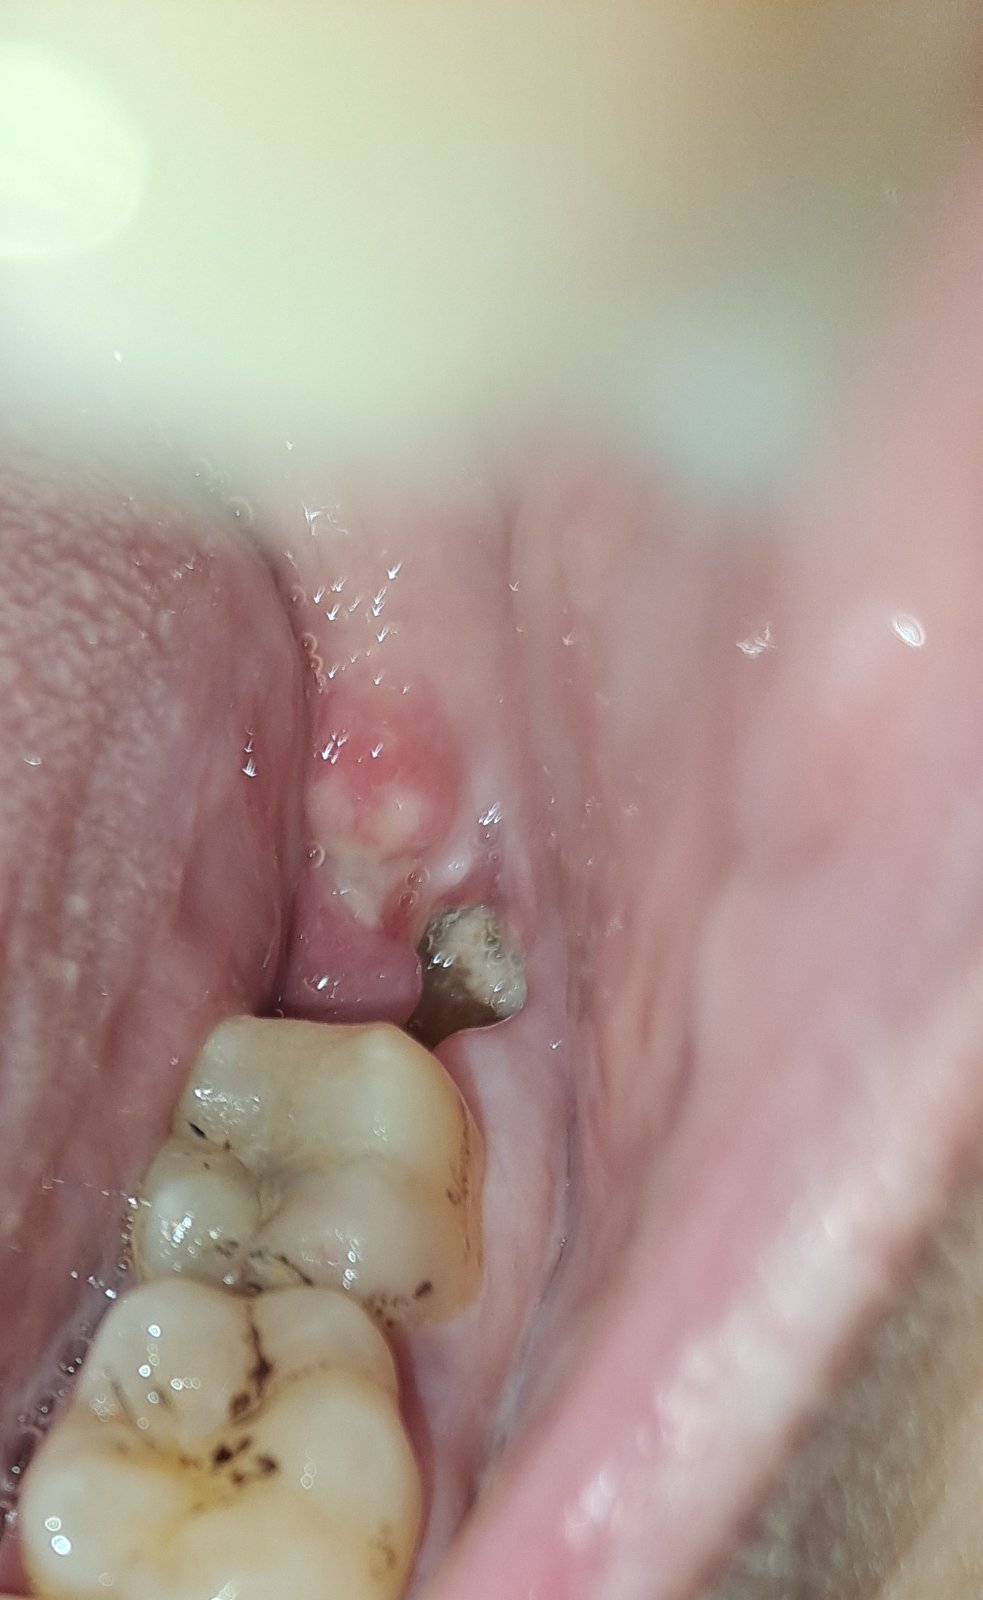

Pozrela som si ranu, zda sa mi mensia, ale mam tam taky biely povlak, teraz neviem, ci je to ten povlak co sa tvori pri hojeni, alebo sa urobilo suche lozko.

@perlicka50 ano ten povlak je ok, to je hojenie